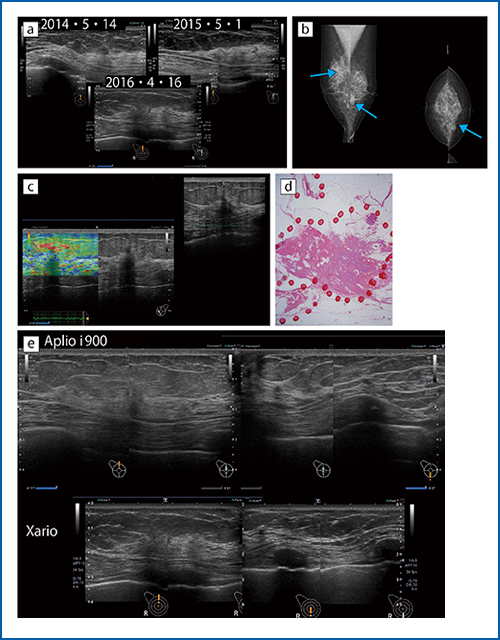

●症例5:非浸潤性小葉癌と硬化性腺症に伴うDCIS

この方は50歳代で,3年間超音波検診のみを受けてきた(図5 a)。2016年の検診画像でも病変は検出できず,「異常なし」の判定となっていた。しかし,半年後に左乳房の窪みを訴え,マンモグラフィを施行したところ,構築の乱れが左右の乳房下部に認められた(図5 b)。一般的に超音波検査は,構築の乱れの検出が難しいとされているが,マンモグラフィを併用し,総合判定を行っていれば,検診での指摘ができたのではないかと考えられる。

本症例の精査をAplio i800で施行したところ,左乳房の病変部のエコーは非常に不明瞭な低エコー域で,エラストグラフィでも明確な歪みの低下はなかった(図5 c)。切除術後の病理診断では,非浸潤性小葉癌とされた(図5 d)。非浸潤性小葉癌は,正常な乳腺構造をあまり壊さず,がん細胞が増殖していくタイプのがんであり,超音波検査では描出が困難である。

右乳房では,後方エコーが局在的に減弱しているものの,病変を拾い上げるのは困難であった。病理診断の結果,硬化性腺症に伴うDCISと診断できた。硬化性腺症の内部にDCISがあるため,病変がまとまっておらず,超音波検査では検出しにくい症例である。

図5 eに,本症例における「Aplio i900」と検診エコーの画像を示す。右12時-6時の連続画像を供覧した。

図5 症例5:非浸潤性小葉癌と硬化性腺症に伴うDCIS

a:過去3年の検診画像 b:マンモグラフィ画像 c:エラストグラフィ画像

d:病理像 e:Xario(下)とAplio i900(上)の比較